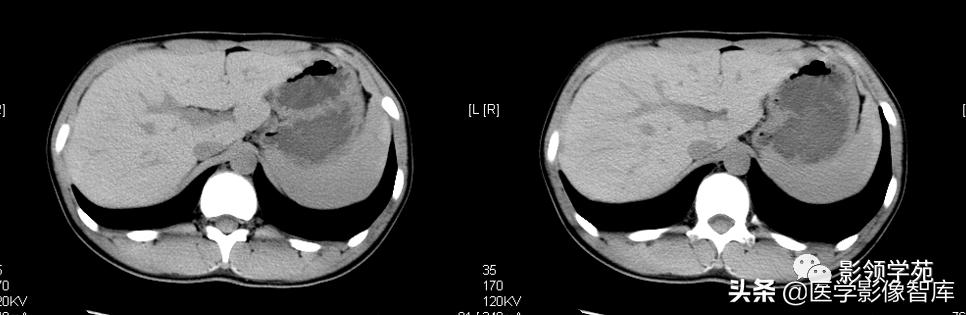

急性期:1)CT平扫:见脾实质内三角形低密度灶,基底位于脾的外缘,尖端常指向脾门,边界清楚或模糊。2)增强扫描:病灶无强化,边界较平扫时更加清楚。

慢性期:1)CT平扫:梗死区密度逐渐增高,脾脏因纤维组织增生和瘢痕收缩而致边缘局部内陷。2)增强扫描:瘢痕组织呈轻微强化的低密度区。